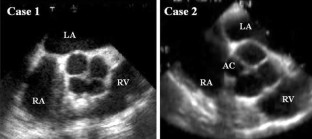

Quadricuspid aortic valve (QAV) is a rare congenital aortic valve anomaly. We present two cases of QAV diagnosed by using echocardiography including transesophageal echocardiography (TEE) and cardiac computed tomography (CT). The first case, QAV with four equal-sized cusps, was identified in a 58-year-old man. The second case, QAV with a small accessory cusp between the right coronary and non-coronary cusp, was identified in a 42-year-old man. TEE and cardiac CT could lead to accurate diagnosis of QAV. QAV in these two patients could be diagnosed before indication for surgery but it is necessary to continue careful follow-up.

Fig. 1